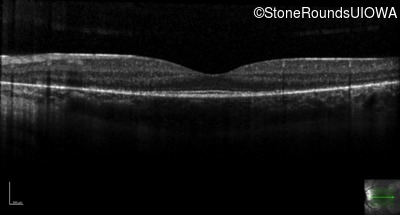

Optical Coherence Tomography - Right - 20/20 -1 sc

Exemplar / OCT Stack

OCT Stack